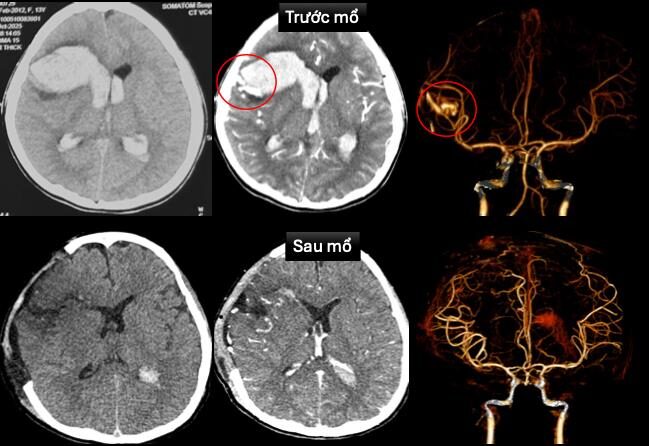

Nếu các bạn có bất kỳ thắc mắc gì về bệnh đột quỵ, hãy đặt câu hỏi cho chúng tôi dưới đây:Cứu sống bé gái 13 tuổi hôn mê do vỡ mạch máu não trên nền bệnh tim hiếm gặp

Một bé gái 13 tuổi hôn mê sâu do vỡ dị dạng mạch máu não, lại mang trong mình căn bệnh tim hiếm gặp – “cơ tim xốp” đã được cứu sống ngoạn mục nhờ sự phối hợp khẩn trương, chính xác giữa các chuyên khoa tại Bệnh viện Nhi Đồng 1.